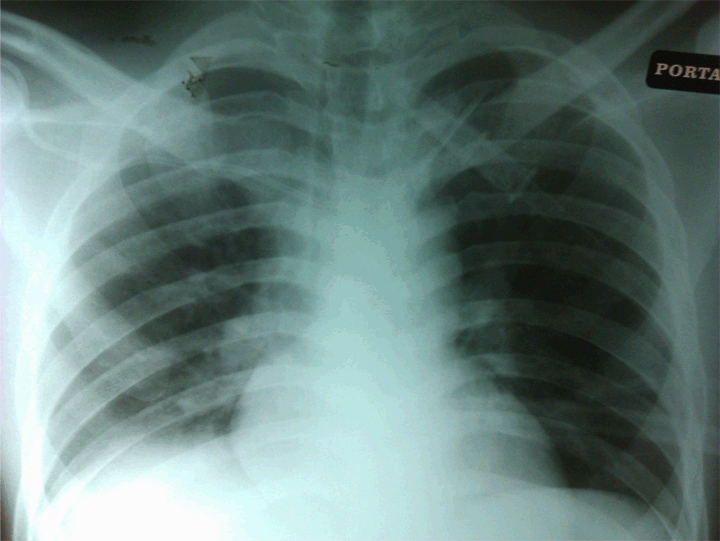

A routine post procedural chest X-ray (Figure 1) was done immediately, but this was not reviewed by the surgical resident until 12 hours later. The chest X-ray appeared to show that the central venous line entered the right subclavian vein, and then traversed the brachiocephalic vein before re-entering the left subclavian vein. There was no pneumothorax or hemothorax noted. The patient had no complains and was not in distress. Therefore, it was decided that the central line should be removed as soon as the patient could tolerate orally, likely to be the following day. However, he began complaining of abdominal pain and increasing dull pain of the right chest throughout the night. He had poor respiratory effort, refused chest physiotherapy and was unable to mobilize out of the bed due to ongoing pain.

Cursor on image to zoom/Click text to open image

Figure 1: Malpositioned right subclavian line.